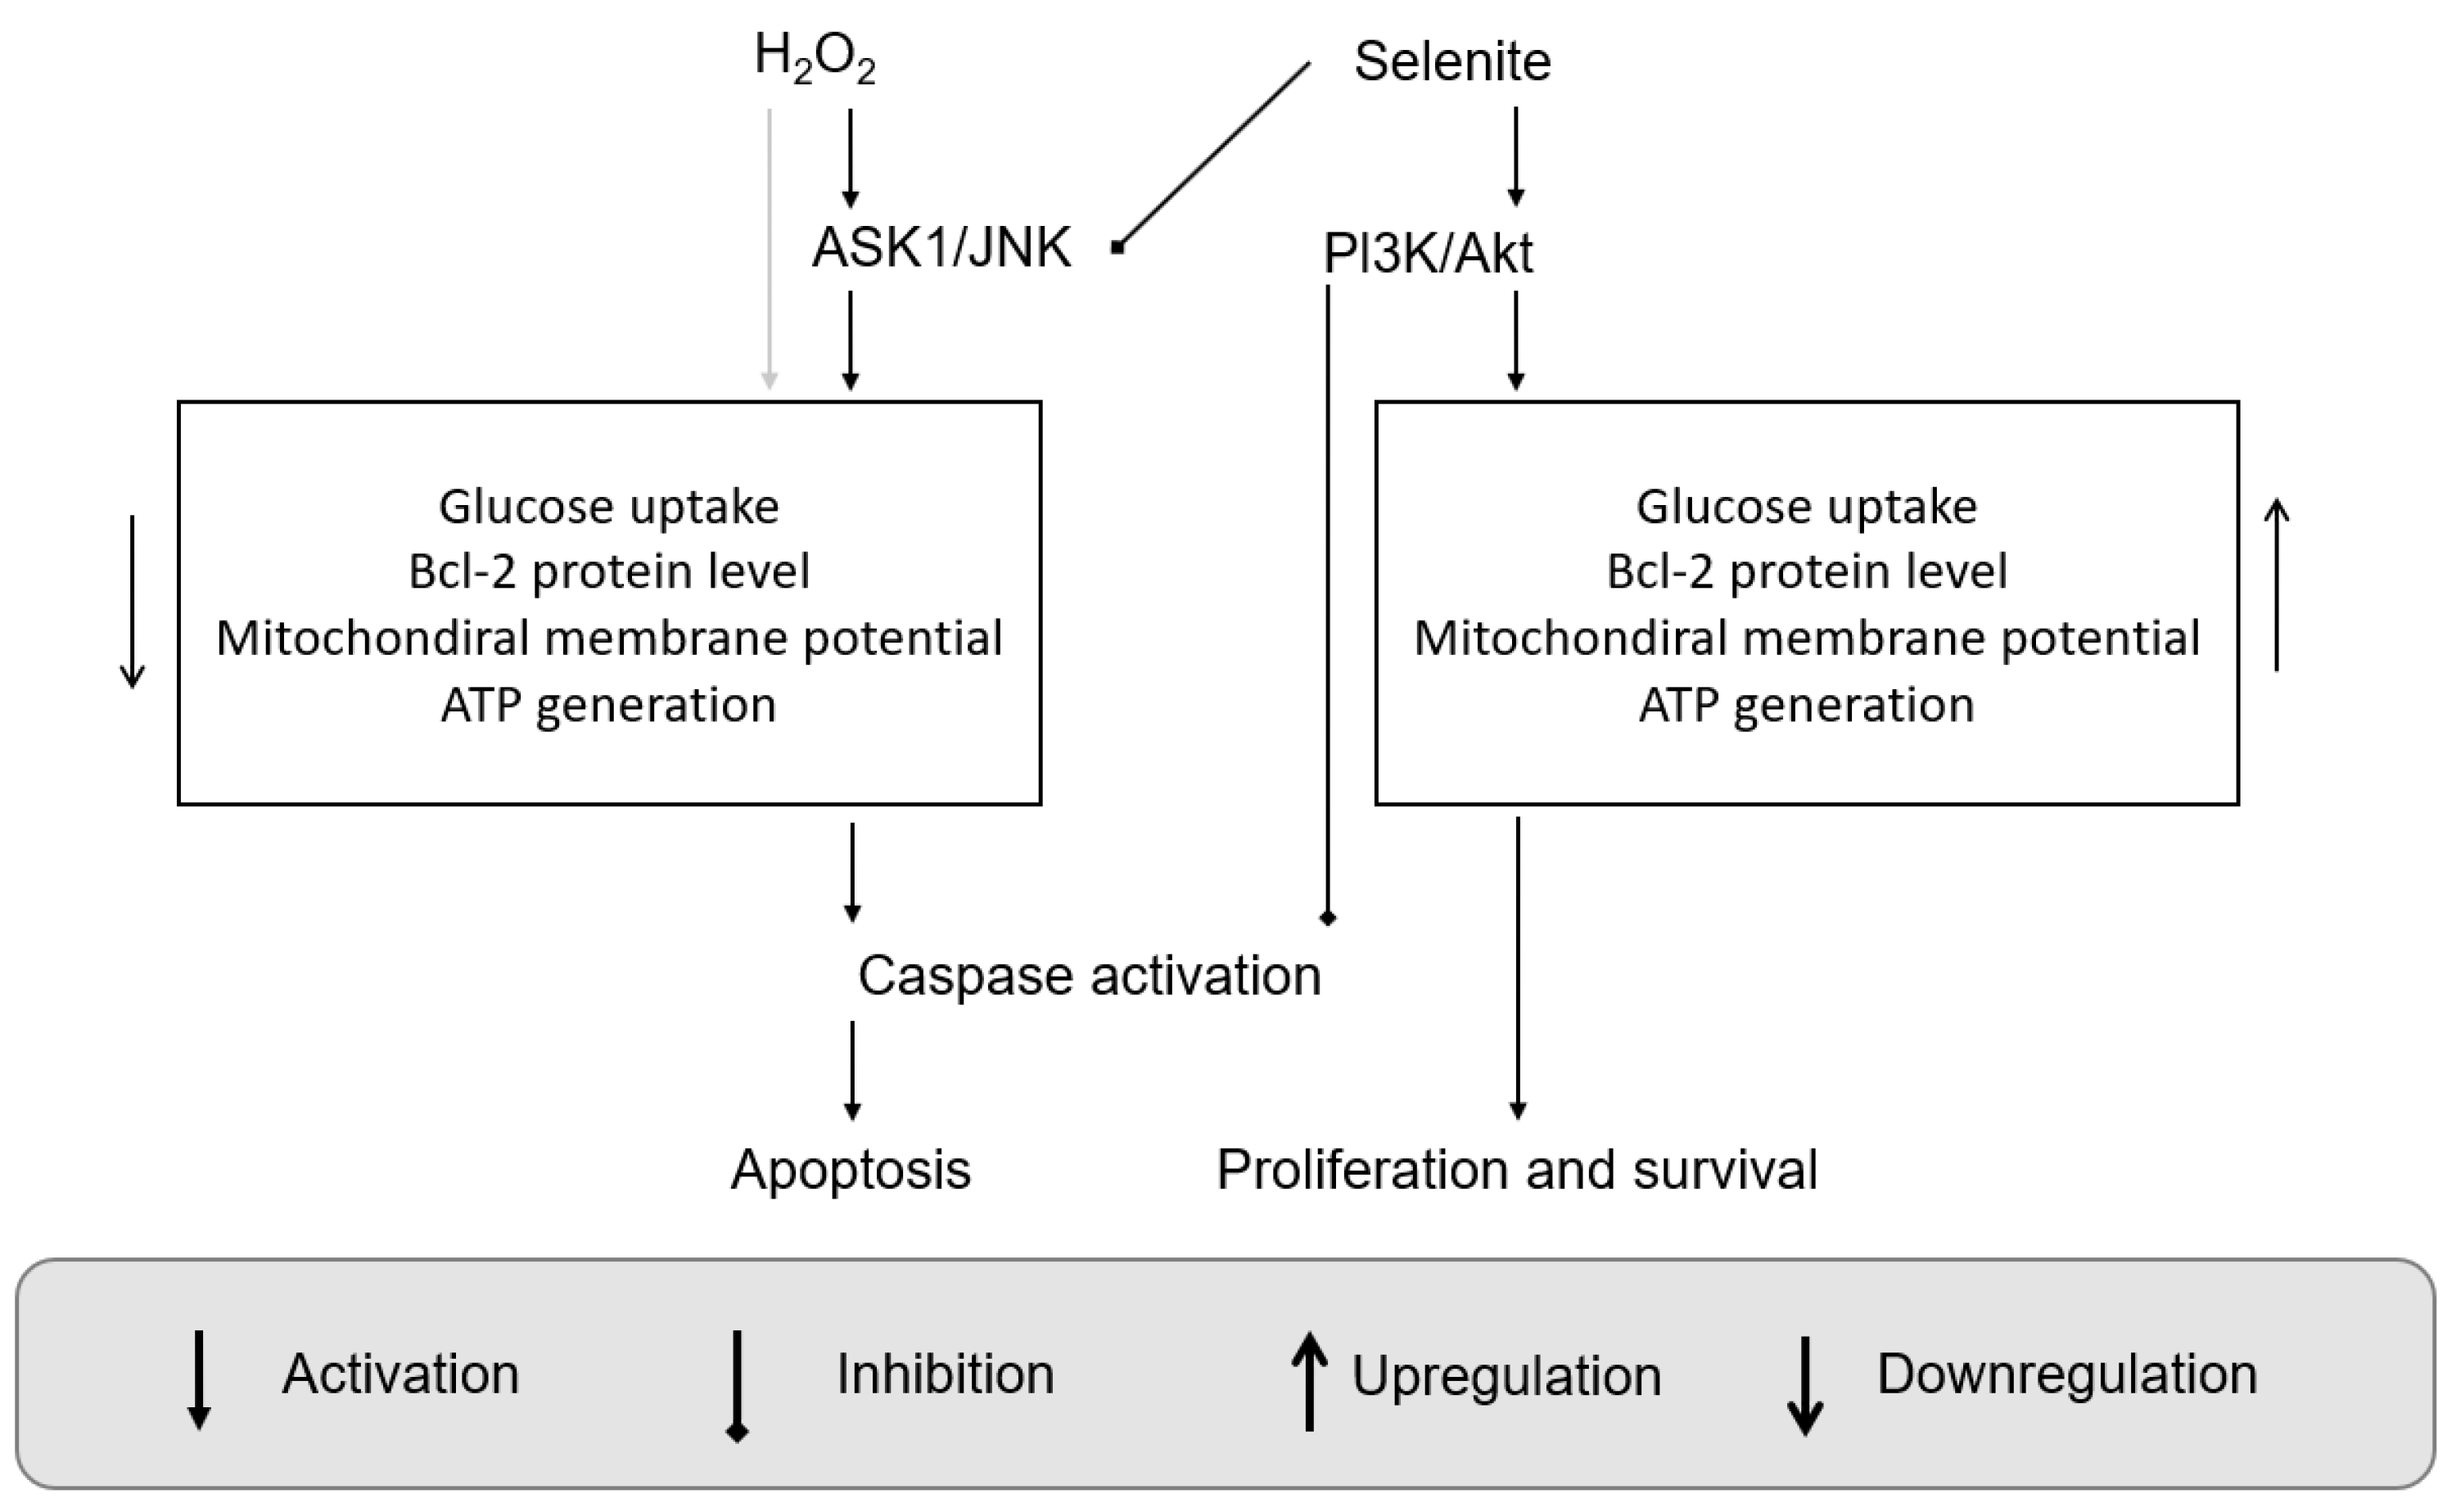

2. Selenium Compounds and Their Metabolism

3. Signaling Pathways and Molecular Targets Pertinent to Biological Selenium

- Further exploration of the (side) effects of Se and Se-containing small molecules on biology is required. One goal of these medicinal studies would be to check the relationship between the induction of Akt activity and the reduction of the ASK1 complex.